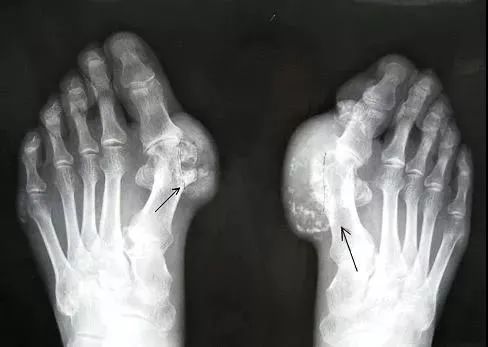

所谓痛风

是由尿酸盐沉积导致的

一种晶体相关性关节病

痛风的病因是「高尿酸血症」

就好比水里的盐浓度太高了

慢慢被析出来就形成“尿酸结晶”导致痛风

痛风石与慢性痛风性关节炎等